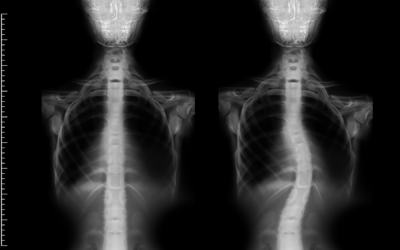

Dr. Arun Hariharan provides compassionate care for spine-related conditions like scoliosis, delivering personalized treatment that empowers children to achieve their best health and mobility.

Dr. Arun Hariharan's expertise includes innovative techniques like Vertebral Body Tethering (VBT) for spinal correction, halo traction, and growth-friendly methods such as MAGEC rods that support a child's growth while managing spinal curvature over time.

Understanding Scoliosis Types: Idiopathic, Congenital, & Neuromuscular

When a parent hears the word 'scoliosis', they often picture a single condition with a single...

What Is Scoliosis? Signs, Symptoms, and When to Seek Help

Scoliosis is one of the most common spinal conditions affecting children and adolescents, yet it's...